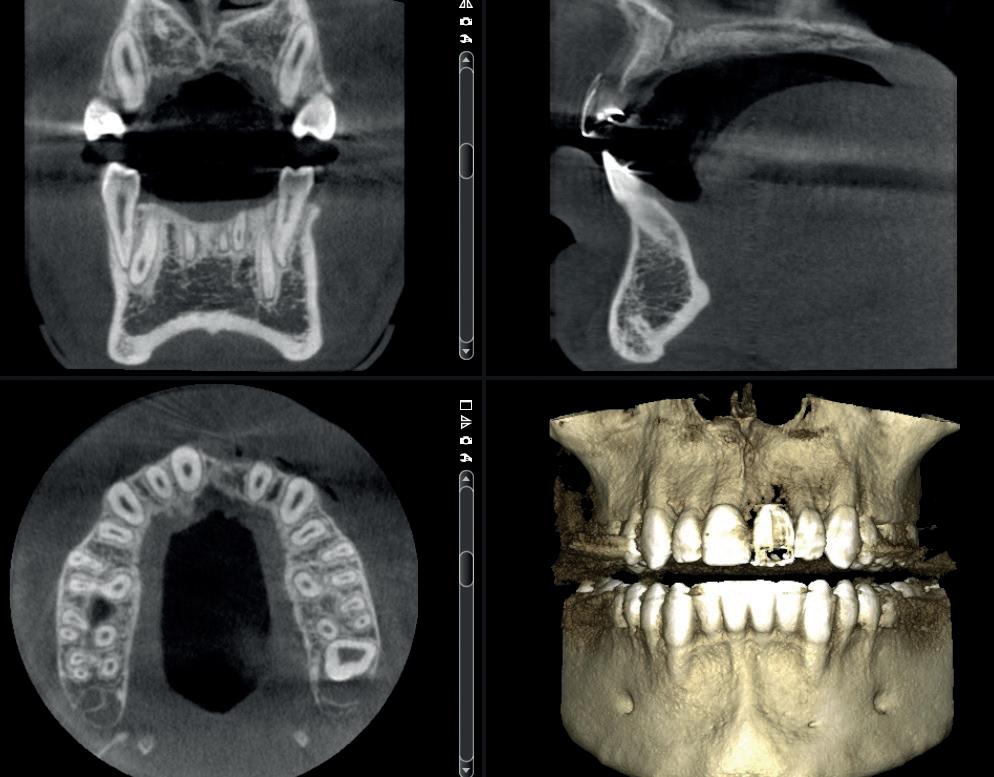

SITE AUGMENTATION Reconstituirea țesutului moale periimplantar și papilar în zona estetică

RECONSTITUIREA țesuturilor moi periimplantare. Scopul acestui raport de caz este de a demonstra procedurile chirurgicale utilizate pentru corectarea unui defect al țesuturilor moi periimplantare folosind țesutul moale interdentar în combinație cu tuberozitatea ca locație donatoare de țesut conjunctiv, utilizând o abordare prin tunelizare într-o zonă estetică.